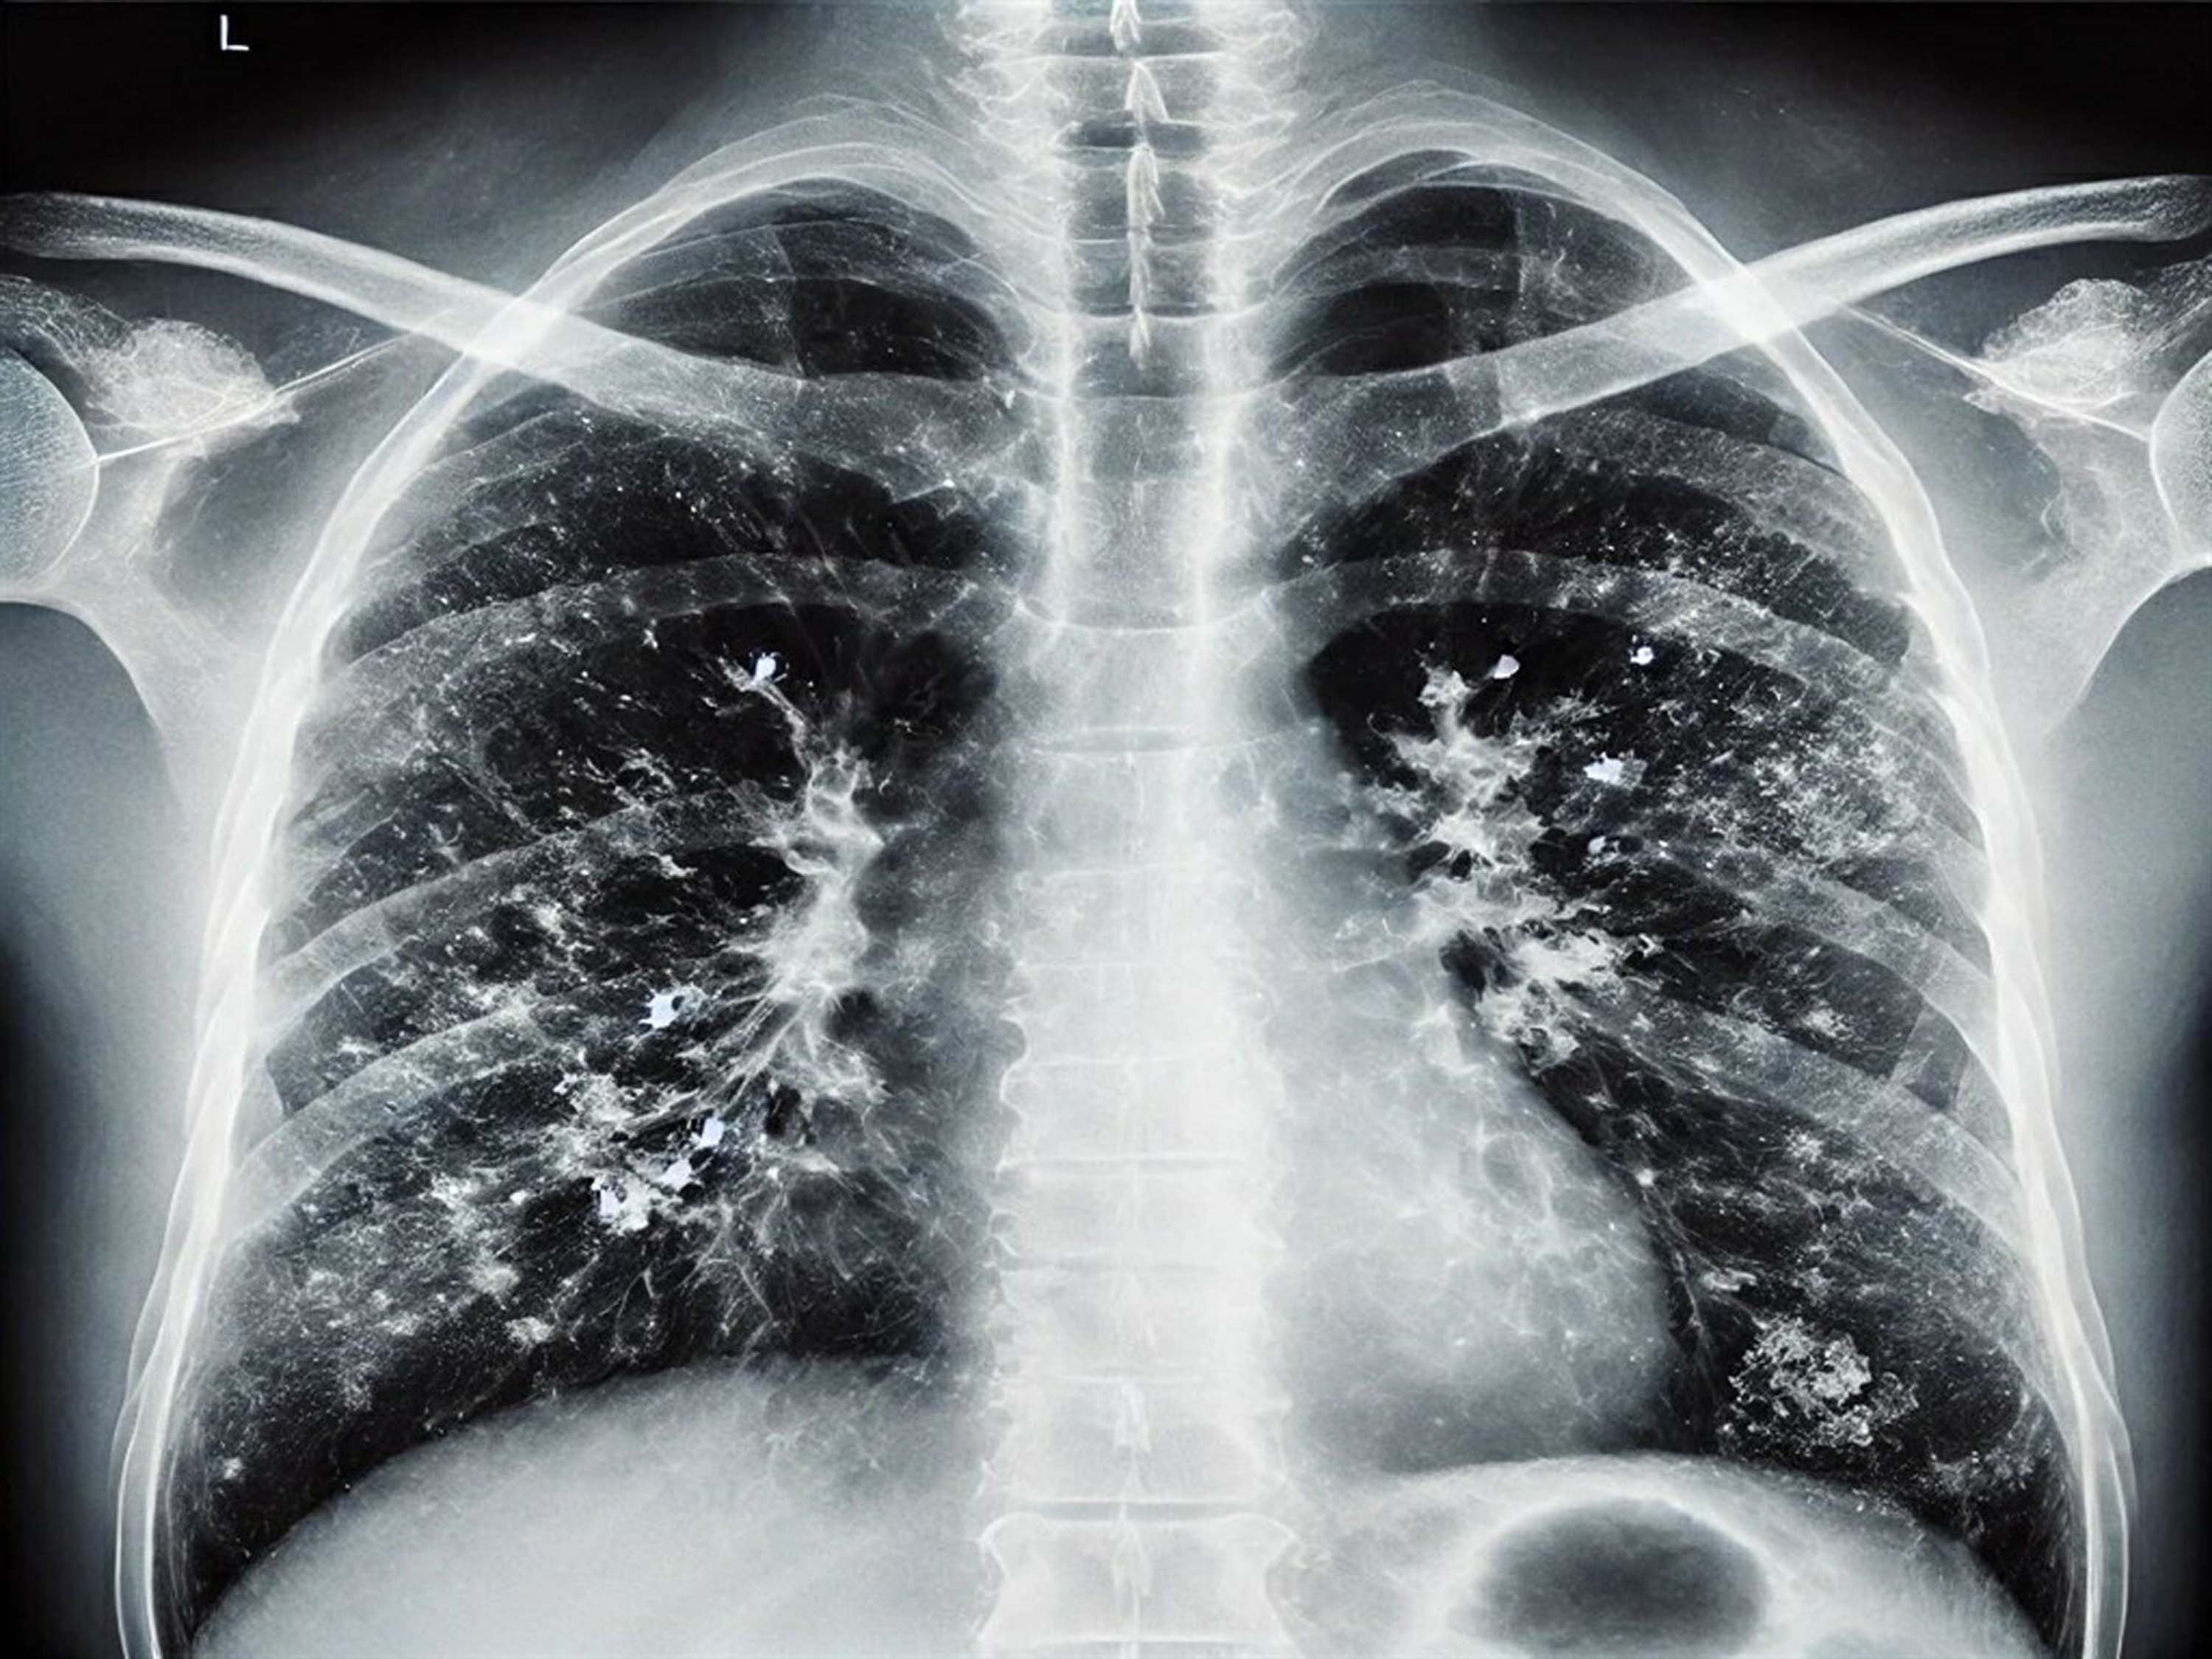

İKÇÜ Atatürk Eğitim ve Araştırma Hastanesi Enfeksiyon Hastalıkları Anabilim Dalı'nda görevli Prof. Dr. Alper Şener, son dönemde viral enfeksiyonlarda artış yaşandığını belirtti. Gribal enfeksiyonlar açısından influenzada ciddi bir yükseliş olduğunu ifade eden Prof. Dr. Şener, "İnfluenza dışında RSV ve rinovirüs de görülüyor. Gribal enfeksiyon geçirdikten sonra bakteriyel enfeksiyonlar, süperenfeksiyon olarak ortaya çıkıyor. Bu süperenfeksiyonlar, bakteriyel olduğunda bazen ağır tablolara neden olabiliyor. Zatürre, pnömoni, akciğer iltihabı gibi durumlar hastaneye yatışa hatta oksijen desteği ihtiyacına sebep olabilecek klinik tablolara yol açabiliyor. Bu açıdan dikkat etmek lazım. Aile hekimine başvurduğunuzda ücretsiz grip aşınızı olabilirsiniz" dedi.

Özellikle 65 yaş üstü vatandaşlara yönelik uyarılarda bulunan Prof. Dr. Şener, "Bu grupta RSV dediğimiz viral enfeksiyon önem taşıyor. RSV, akciğerde yaygın enflamatuar tabloya sebep oluyor. Bunun da aşısı var. Cebinizden ücret ödeyerek yaptırabileceğiniz bir aşı. Özellikle 75 yaş üstü bireylerin mutlaka olması gerekiyor. 65 yaş üstünden başlarsak viral enfeksiyonlar ağır seyrediyor. Koronavirüs döneminde bunlara alışkındık; pandemi sonrasında da ağır viral enfeksiyon tablolarıyla karşı karşıya kalmaya başladık. Ciddi solunum yetmezliği, ateş, üşüme ve titreme semptomları; acil servise başvuru ve oksijen desteğine rağmen toparlanamama gibi durumlar görüyoruz. Bu nedenle bu hastalar, bazen normal servise bazen de yoğun bakıma yatmak zorunda kalıyor. Bu hastalar maalesef bazen her türlü tedaviye rağmen akciğerdeki ağır enfeksiyonun yaygınlaşmasıyla ölüme kadar ilerleyebilen klinik tablolara sebep olabiliyorlar" diye konuştu.

Hastalığı ayakta geçirenlere yönelik de değerlendirmelerde bulunan Prof. Dr. Şener, "Hafif geçirseler bile akciğerlerdeki hasar ilerleyen dönemlerde KOAH ve astım gibi tablolara sebep olabiliyor. Sonrasında ömür boyu ilaç kullanmak zorunda kalıyorlar. Bu konu da önemli. Bir diğer tablo ise kalp hastalığı, hipertansiyon ve diyabeti olanlar. Bu kişiler de ağır klinik tablolar geçiriyor. Atlattıktan sonra bakteriyel enfeksiyonlar sık görülüyor. Viral enfeksiyonu hastanede atlattıktan sonra geçmeyen öksürük nöbetleri ve balgam yaşanıyor. Bundan sonra da zatürre dediğimiz tablolar oluşuyor. Bu durumda kesinlikle antibiyotik alınması lazım. 65 yaş üstü gruba mesaj gitmesi gerekirse; hafif bir gribal enfeksiyon geçirdikten sonra öksürük ve balgam devam ediyorsa, uzman doktora veya aile hekimine mutlaka görünmek gerekiyor. Belki de zatürre oldunuz ve farkında değilsiniz. Gerekli tetkiklerin yapılması ve antibiyotik başlanması lazım" dedi.